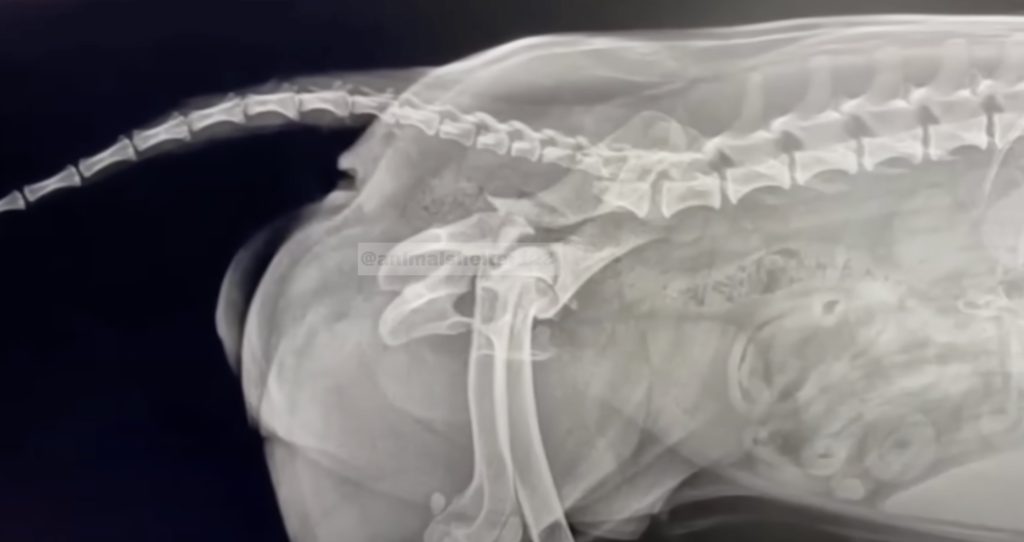

The team began with blood work, an ultrasound, and an electrocardiogram. To everyone’s relief, her internal organs were unharmed. But the X-rays and CT scan told a different story. The images showed extensive fractures in the pelvis, damage to the lumbar spine, and a completely detached tail. The surgeons gathered to discuss possible treatments, but the conclusion was grim. Operating could lead to permanent paralysis or worse.